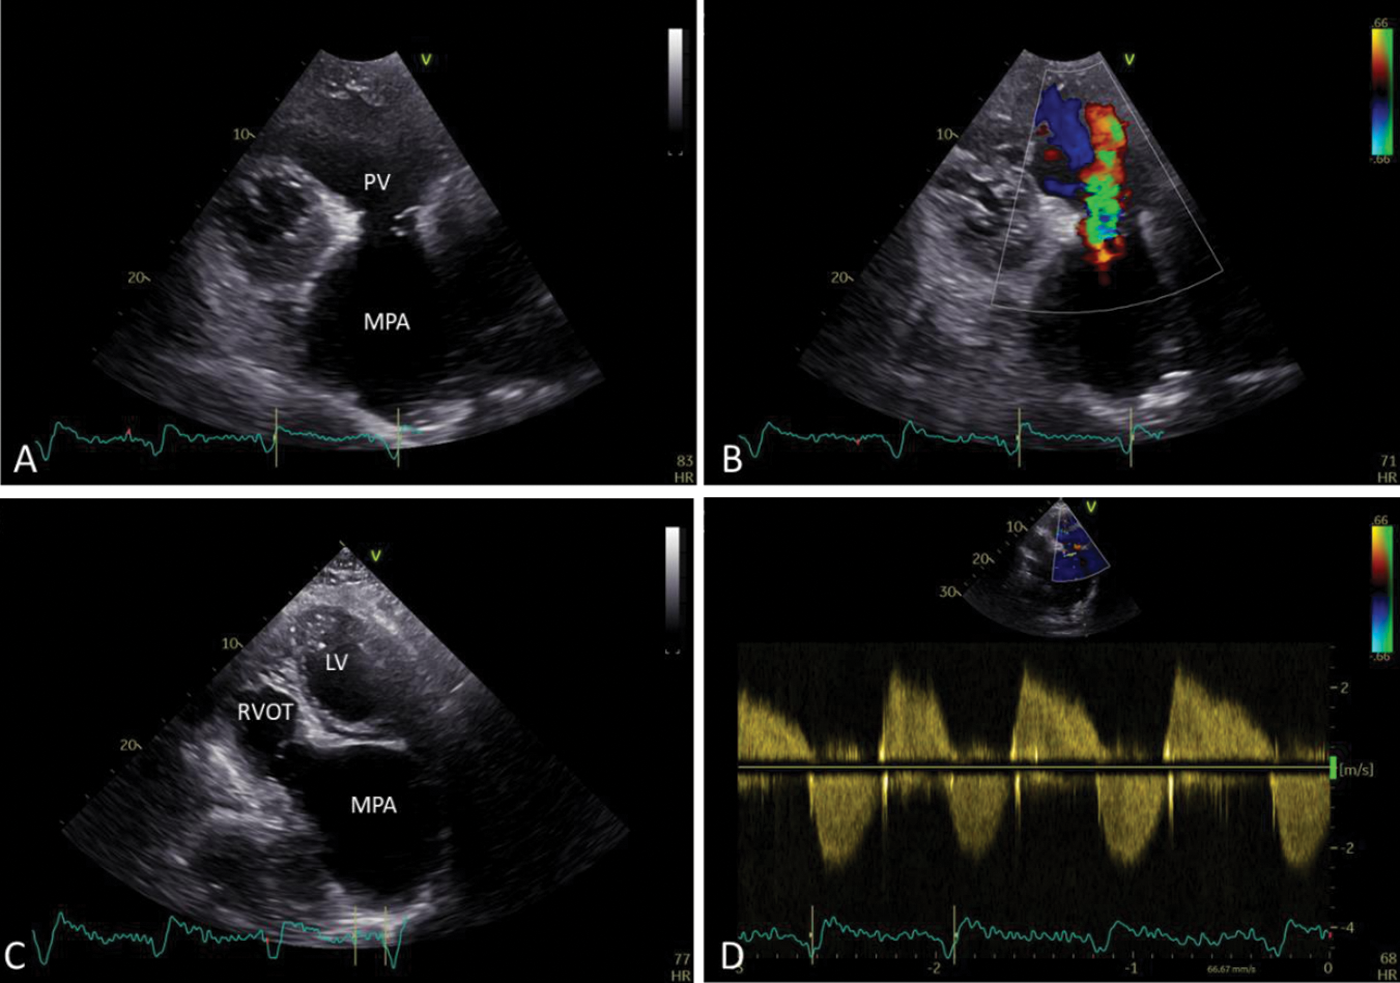

Figure 2: (A) Short axis view–abnormal pulmonary valve (PV), severely dilated main pulmonary artery (MPA); (B) Moderate pulmonary regurgitation; (C) Apical five-chamber view with the further anterior tilt of the probe–giant pulmonary artery (LV-left ventricle; RVOT-right ventricle outflow tract; MPA-main pulmonary artery); (D) Spectral doppler shows moderate pulmonary regurgitation and mild pulmonary stenosis